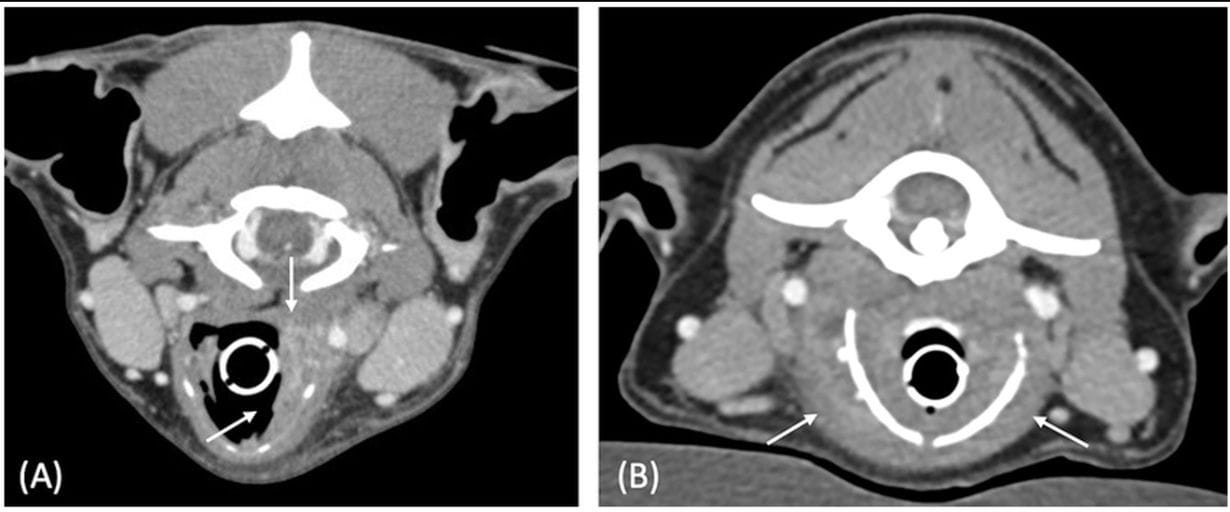

Figure 2. Postcontrast transverse CT images of case 3 (A) and case 6 (B), illustrating the thickened aspect of the laryngeal lesions (white arrows). Both cases had laryngeal masses with mixed external and internal growth pattern, characterized by an increase in thickness on each side of the cartilage. Window width = 400 HU, window level = 40 HU.

Seven dogs were included (median age 9 years). Four cases were neoplastic (all carcinomas) and three inflammatory. Dysphonia was the most common clinical sign. CT findings revealed that all neoplastic lesions appeared ovoid-shaped, whereas inflammatory lesions presented as laryngeal thickening. Both lesion types shared features such as ill-defined margins, heterogeneous contrast enhancement, cavitation (2/4 neoplastic, 2/3 inflammatory), and occasional mineralization. Cartilage destruction was observed in both groups. Regional lymphadenopathy was present in all but one case, with heterogeneous enhancement in tumor cases and more homogeneous enhancement in inflammatory cases.